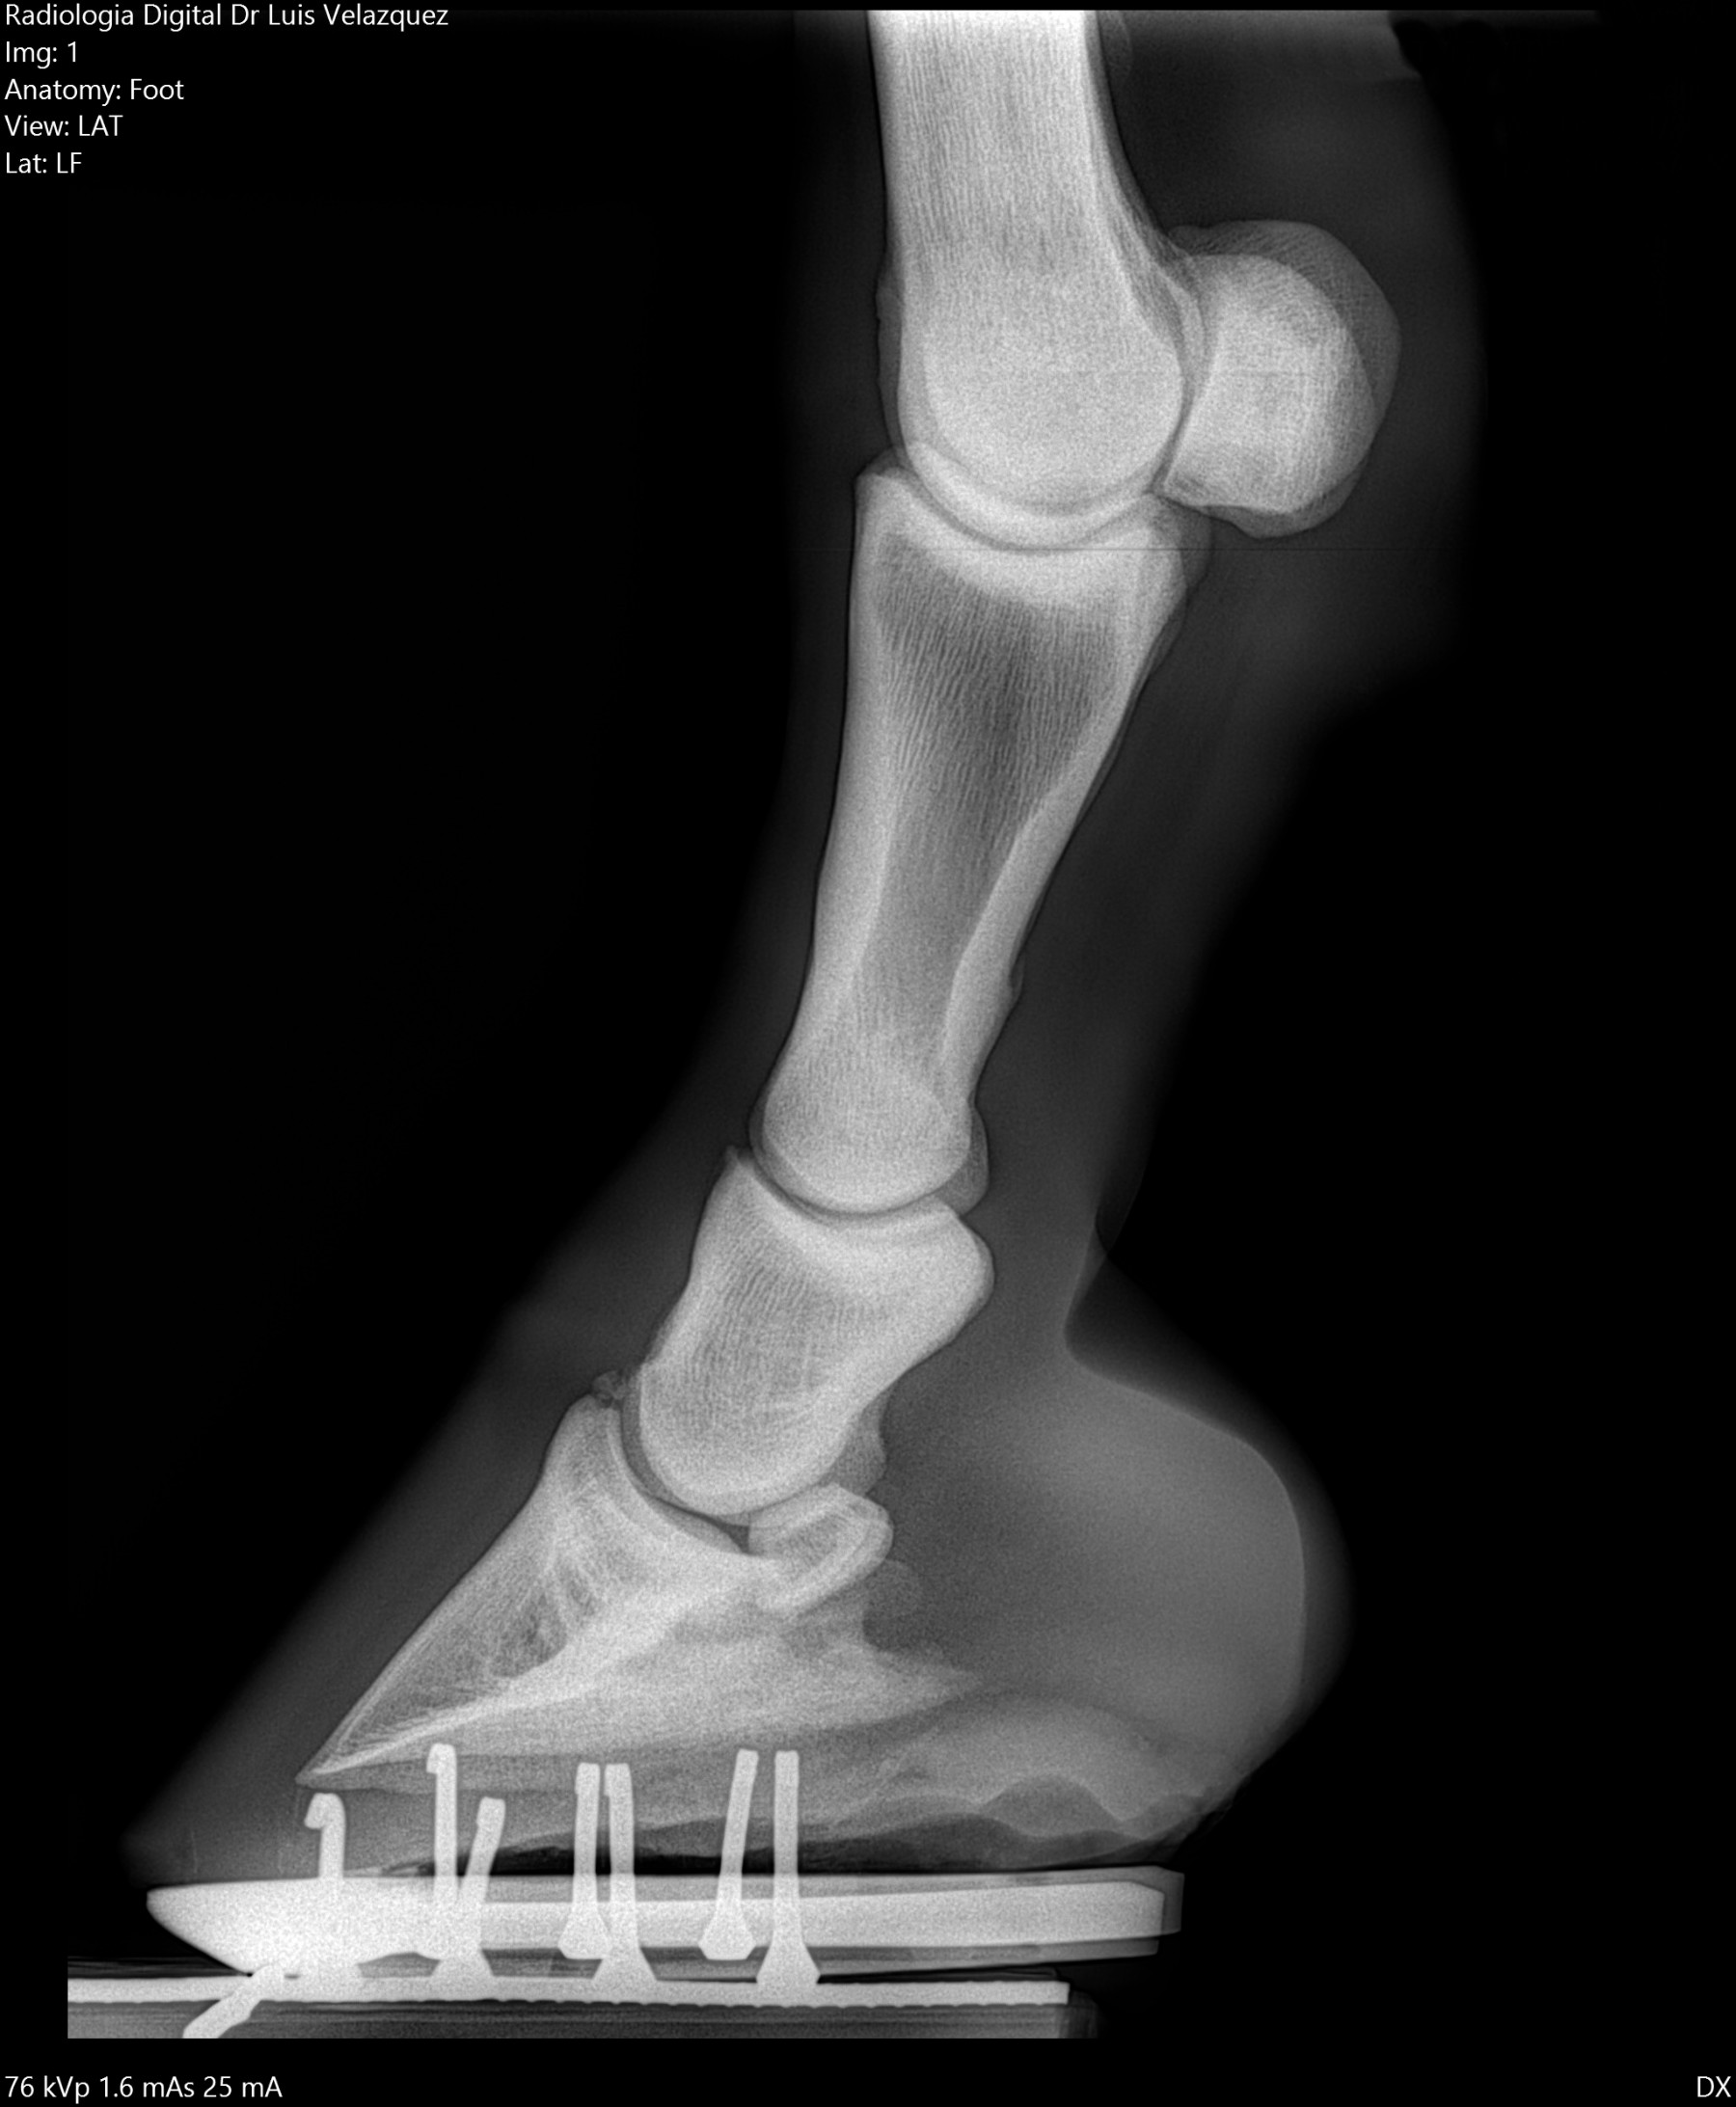

Cambios Térmicos en las Extremidades de Caballos,

Asociados a Golpes y su Evaluación por Termografía.

Los caballos de salto, en competencia, pueden derribar obstáculos y lastimarse. Si se golpean, no siempre claudican. Considerando al calor como un signo de inflamación, se evaluaron los cambios térmicos de 6 áreas de las extremidades torácicas y pelvianas de 23 caballos de salto en nivel de competencia de 1.05 a 1.60 m de altura, por medio de termografía durante 4 días de competencia (N=2208 áreas).